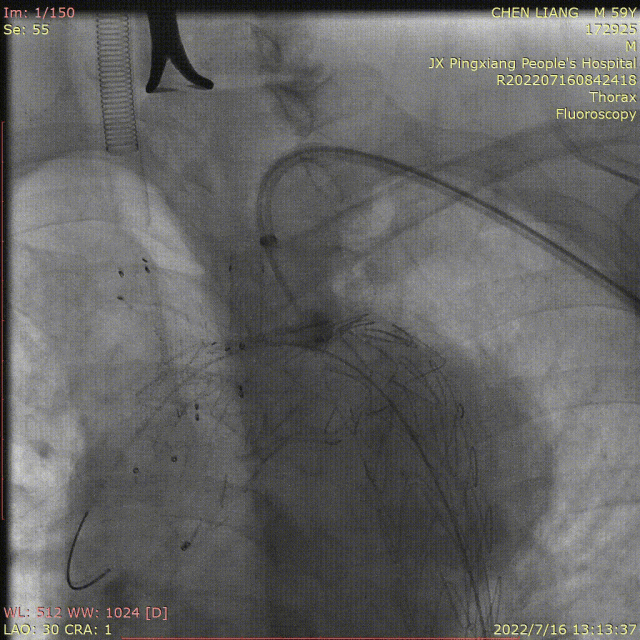

临床应用:医源性夹层:Castor分支支架+迷走右锁骨下动脉原位开窗(需90度角度配合特殊导丝完成)

逆撕A型夹层:Castor分支支架联合迷走左椎动脉预开窗。

弓部动脉瘤:Castor联合内嵌分支LSA预开窗术,目的为防内漏

避免转流的复杂病例:Castor+原位及预开窗(免转流三开窗)治疗弓部动脉瘤